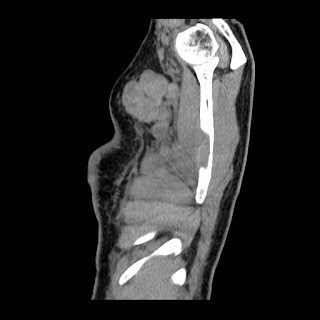

A 62 years old man with enlarged mole on chest since 2 months.

CT chest :-